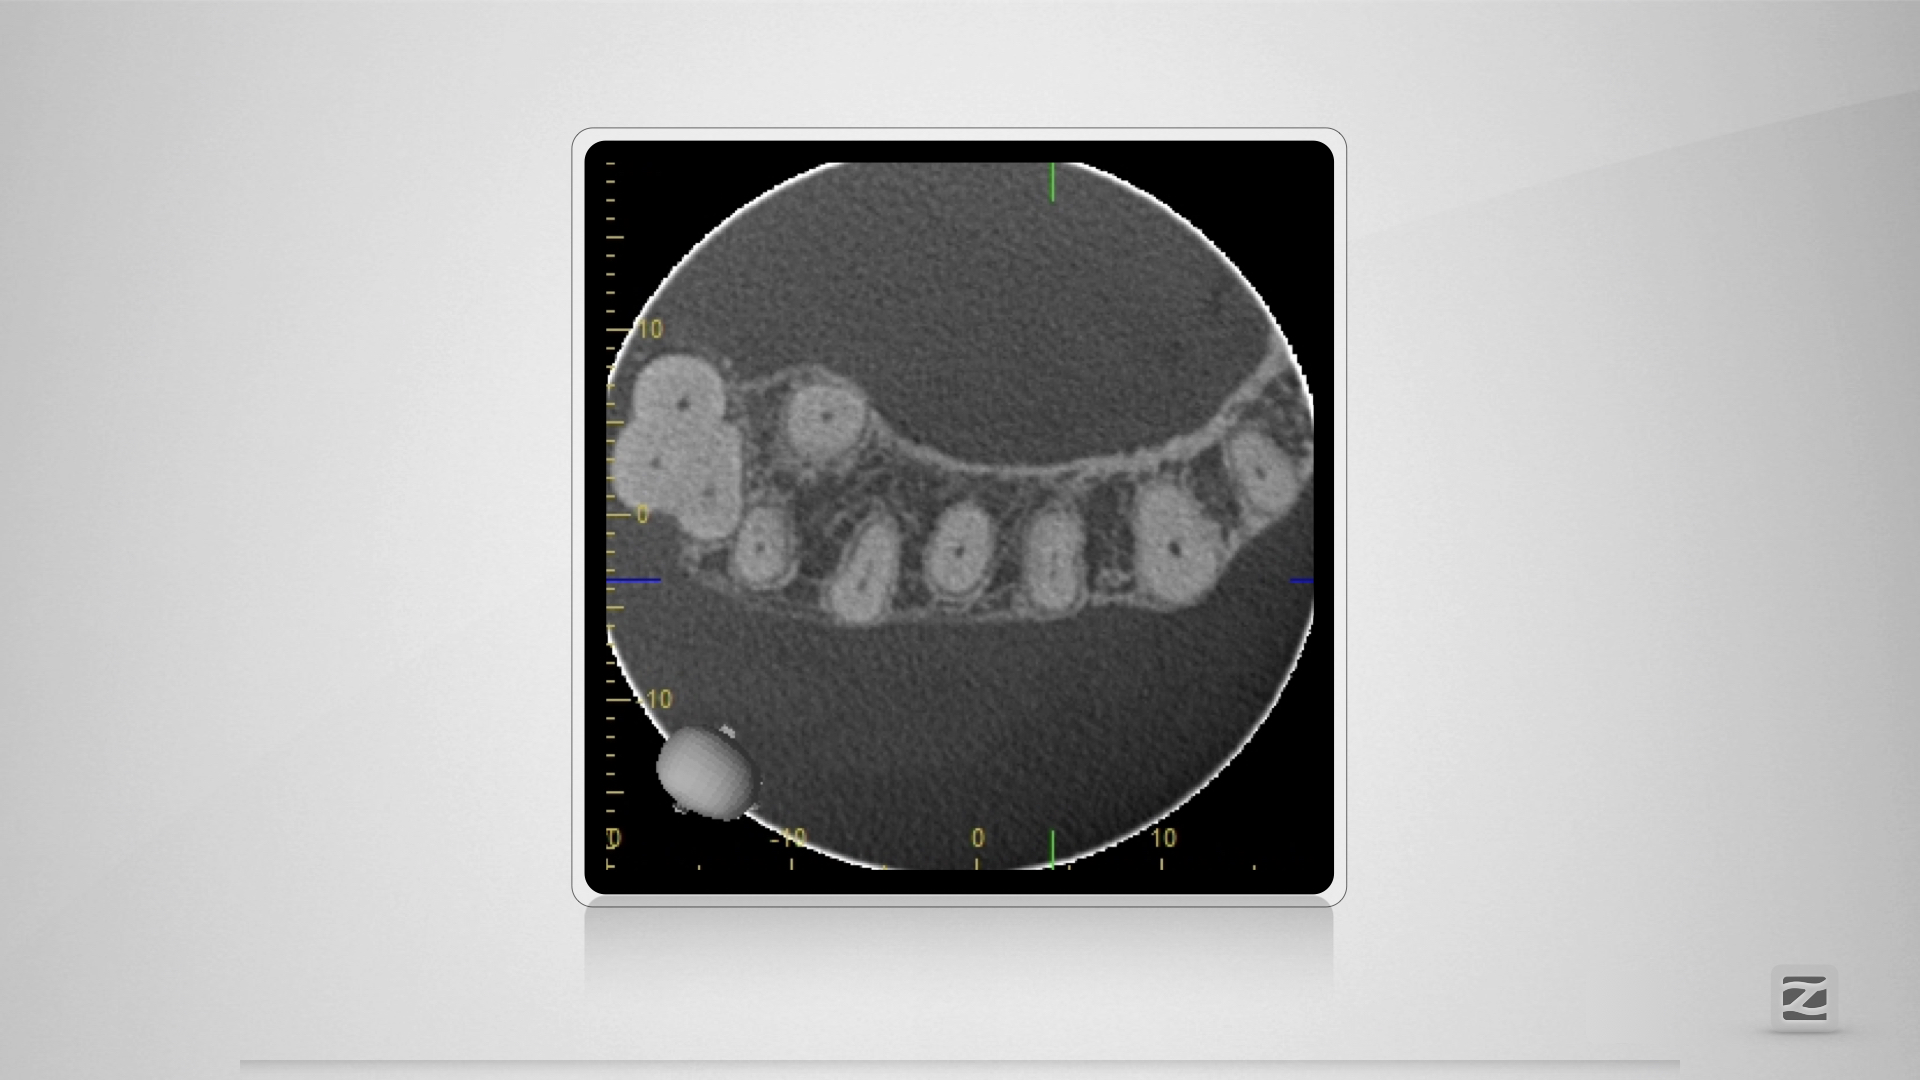

H mit kleiner Tücke